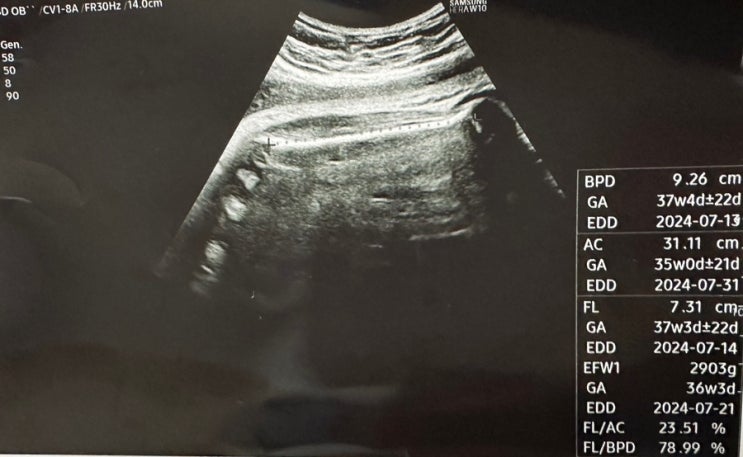

[37주차 기록] 분만전 마지막 진료, 제왕절개 준비, 삼성창원병원 분만

7월이 되면서 출산이 10일도 남지않았다는 사실에 설레는 마음 반 걱정되는 마음 반으로 마지막 진료를 보...